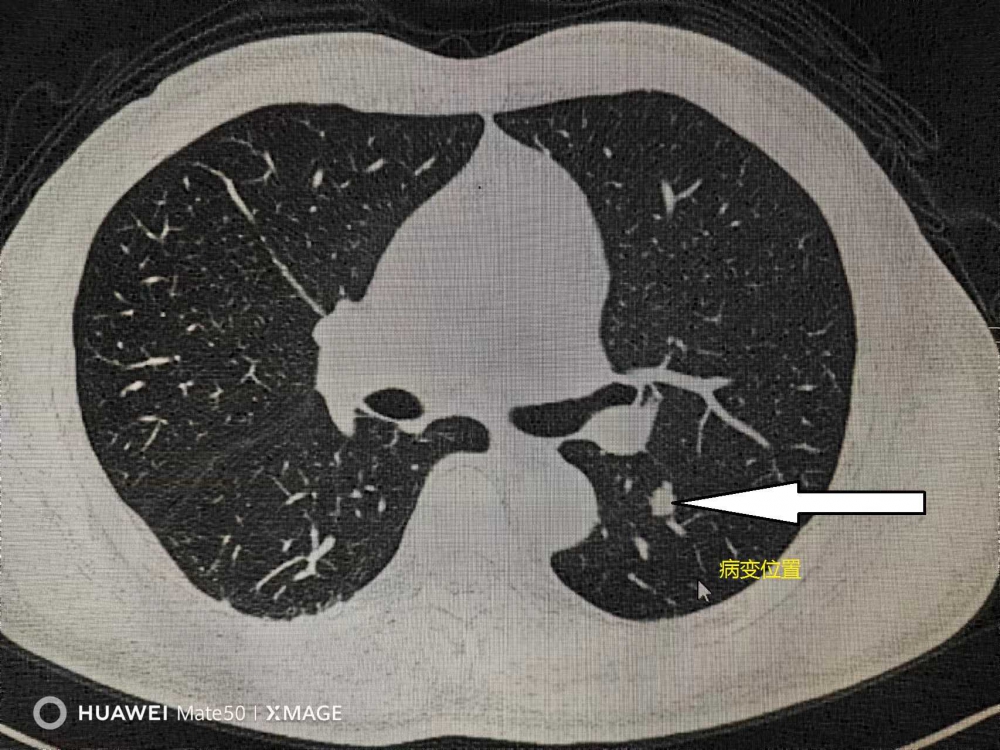

2023年12月23日,家住本地的袁某因查體發(fā)現(xiàn)左肺下葉一0.9cm×0.5cm實性結(jié)節(jié),診斷為左肺下葉占位性病變。因年齡較大,合并糖尿病、前列腺手術(shù)史等基礎(chǔ)疾病,且病變位于左肺下葉背段,袁某本計劃在北京協(xié)和醫(yī)院手術(shù),得知家門口就有北京協(xié)和醫(yī)院專家坐診手術(shù),遂入住我院胸外科治療。入院后胸外科主任季運來會同麻醉團隊,并邀請北京協(xié)和醫(yī)院胸外科專家共同討論研究,決定為患者行胸腔鏡下標準左側(cè)下葉背段切除術(shù),此方案可最大限度的保留其肺功能,利于術(shù)后快速康復。該手術(shù)需要更精細地解剖肺門血管和支氣管結(jié)構(gòu),操作難度遠遠大于普通的肺葉切除術(shù)。手術(shù)于去年12月27日順利完成,并平穩(wěn)渡過圍手術(shù)期,無任何并發(fā)癥,于1月3日康復出院。